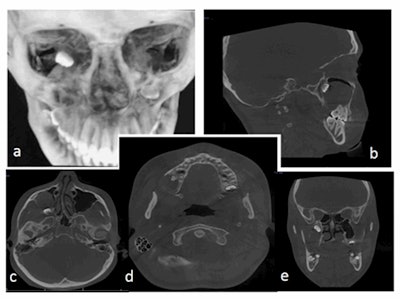

To get a better view, the patient underwent a CBCT scan. The scan showed that the teenager's ectopic third molar had incompletely formed roots located in the posterosuperior aspect of the right maxillary sinus with a close approximation to the orbital floor superiorly and pterygoid plates posteriorly. The lesion measured 23 × 36 × 35 mm, occupied almost the entire cavity of her right maxillary sinus, caused mediolateral expansion of the alveolar ridge, and encapsulated the tooth. The scan also showed how the lesion was obliterating the right maxillary sinus floor and buccal cortical plate. This explained why the girl was experiencing discharge, the authors noted.

She recovered without further incident. During a three-month follow-up visit, she underwent another CBCT scan that showed some bone formation in the mediolateral dimension, which indicated that the bone had started to heal.